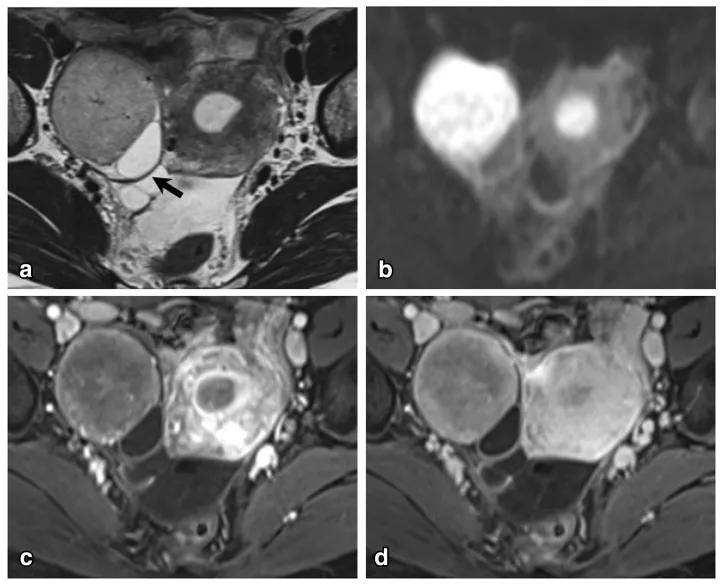

女,70 岁,卵泡膜细胞瘤。图 a 增强扫描显示右侧卵巢肿物(白箭),同时子宫内膜增厚(图 a 白箭头及图 b 黑箭)。

女,68 岁,左卵巢 Brenner 瘤。T2WI 显示左侧卵巢巨大低信号肿物(图 a),CT 扫描显示 8 年后肿物增大、多发钙化、发生囊变(图 b)。